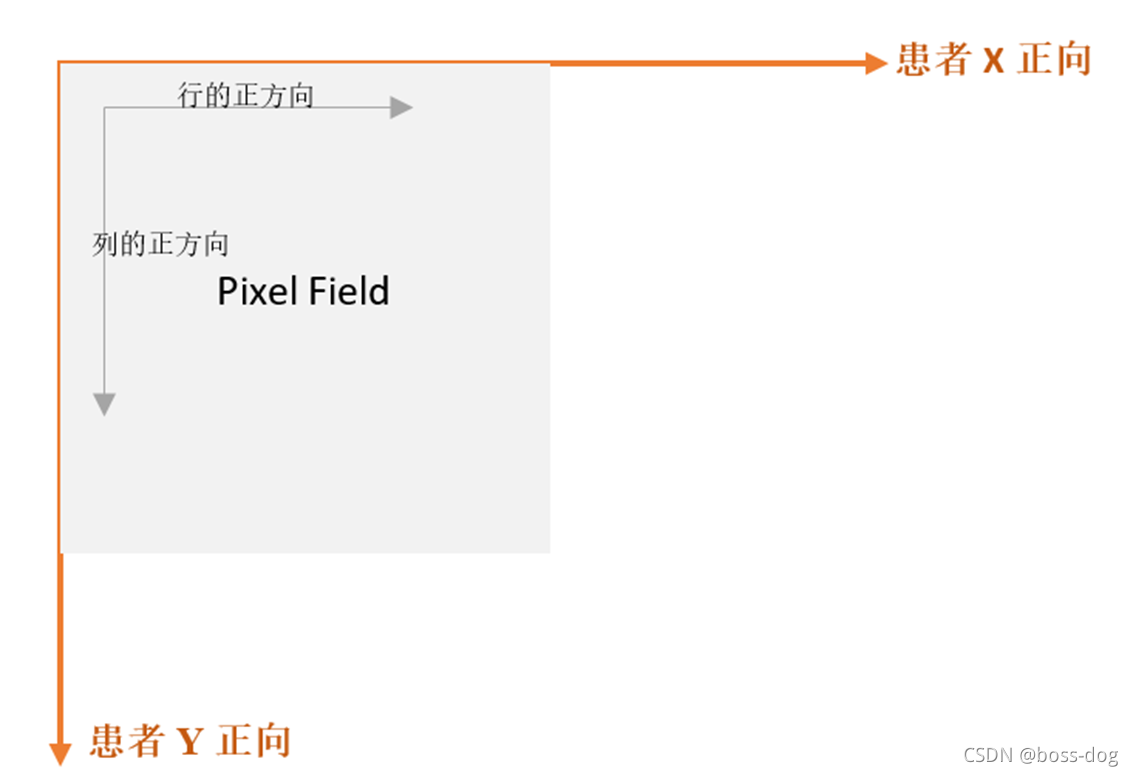

Image Orientation-1

DICOM3.0格式影像文件中和坐标有关的部分主要是以下几个数据元素:

- (0018,5100) Patient Position CS 1

- (0020,0032) Image Position (Patient) DS 3

- (0020,0037) Image Orientation (Patient) DS 6(用来表示斜着的轴状位、冠状位、矢状位)

- (0028,0030) Pixel Spacing DS 2(用来表示图片中每个像素所代表的X和Y水平方向和竖直方向的尺寸是多少、像素有多大)

- (0018,0050) Slice Thickness DS 1(用来表示切很多层,那每一层的厚度是多少)

Image Orientation-3

- (0020,0032) Image Position (Patient)描述了该张影像首个像素(“左上方”)的坐标,这个数据元素和(0020,0037)一起确定了该张影像中所有像素的坐标,用3个不超过16字节的字符串存放。分别是X,Y,Z值。

- (0020,0037) Image Orientation (Patient)是一个非常重要的数据元素。由6个不超过16字节的字符串存放。

在这里先要说明一下,在DICOM 3.0中坐标轴的指向完全以病人为准。以病人中心为原点,病人左手指向的方向为X轴正向,病人背后的方向为Y轴的正向,往病人头部的方向为Z轴的正向。因此是一个以病人为中心的右手坐标系。

Image Orientation-4

Image Orientation-5

(0020,0037) 的前三个数字代表分别代表行向量(行递增方向)和X,Y,Z轴夹角分别的余弦值(Cosine),后三个数字分别代表列向量(列递增方向)和X,Y,Z轴夹角分别的余弦值。这样就能精确计算出该张影像中每一个像素点在坐标系中的位置,对于多排螺旋CT产生的影像序列来说,这个意义尤其重大。

- 横断面:(1,0,0)(0,1,0)

- 冠状面:(1,0,0)(0,0,-1)

- 矢状面:(0,1,0)(0,0,-1)